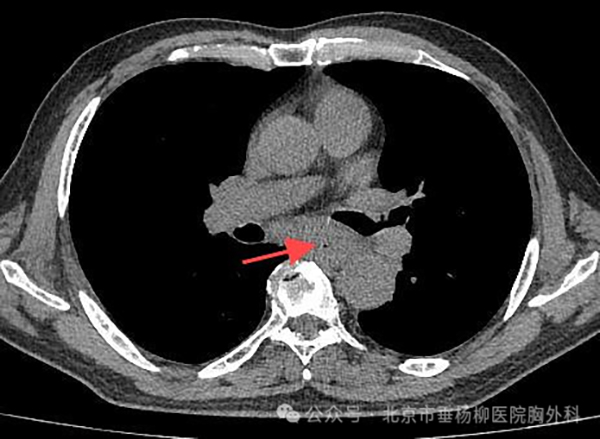

【垂医病例科普】胸外科:硬质支气管镜让…

【垂医病例科普】胸外科:不容忽视的吞咽…